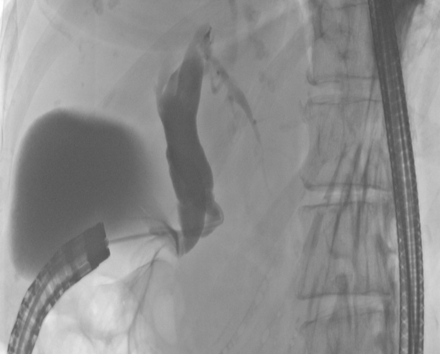

Abdominal ultrasound showed a distinct intra- and extrahepatic widening of the biliary tract and 2 prepapillary gallstones in the main bile duct. Blood tests showed increased values for GOT, GPT, γ-GT, AP, and CRP. The values for bilirubin and lipase were normal. Esophagogastroduodenoscopy (EGD) revealed a stenosis of the pylorus and an erosive duodenitis with a postpyloric diverticulum and concurrent antral gastritis. Furthermore there was an ectopic orifice with biliary secretion in the prepyloric stomach. A normal papilla in the duodenum was not found. Endoscopic retrograde cholangiopancreatography (ERCP) with selective intubation of the prepyloric orifice showed a very short and widened biliary tract (Figure 1 [Fig. 1]). Choledocholithiasis could not be confirmed. A magnetic resonance cholangiopancreatography (MRCP) scan confirmed the ectopical drainage of the lightly widened common bile duct into the prepyloric region (Figure 2 [Fig. 2]). Enlarged lymph nodes in the hepatoduodenal region were present.

Figure 1: ERCP with gallbladder and widened bile duct